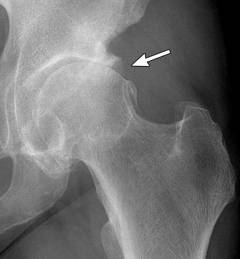

Остеофиты чаще всего возникают в крупных суставах, таких как коленный и тазобедренный, где нагрузка максимальна.

Остеофиты могут образовываться и в полости суставов, чаще всего в коленном, плечевом и тазобедренном суставах, в результате деформирующего остеоартроза.

На начальных стадиях остеоартроза остеофиты представляют собой заострения до 1–2 мм, формирующиеся на краях суставных поверхностей. По мере прогрессирования остеоартроза остеофиты увеличиваются в размере.